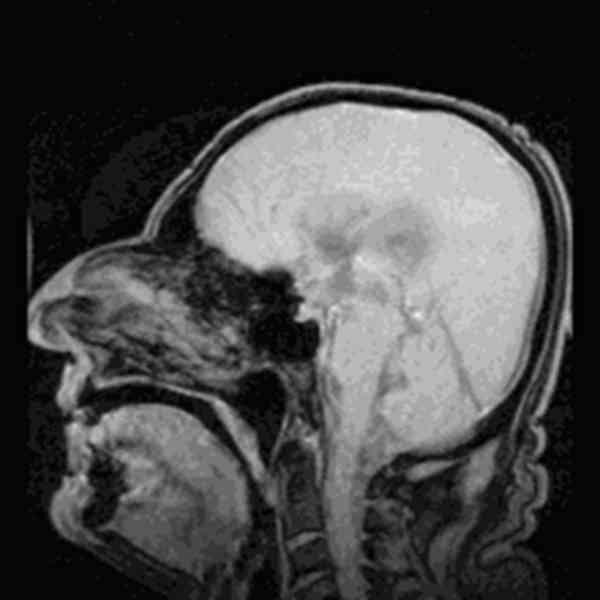

左图是大脑表层,右图是大脑内部,红色代表血管

脑脊液(绿色)并不会只在外层呆着,相反,它会沿着脑血管外壁回流。在回流的过程当中带走细胞间隙的垃圾和毒素。